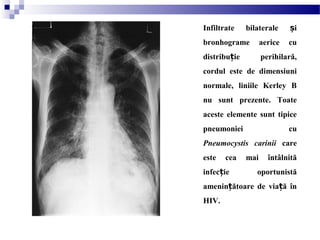

Infiltrate bilaterale iș

bronhograme aerice cu

distribu ie perihilară,ț

cordul este de dimensiuni

normale, liniile Kerley B

nu sunt prezente. Toate

aceste elemente sunt tipice

pneumoniei cu

Pneumocystis carinii care

este cea mai întâlnită

infec ie oportunistăț

amenin ătoare de via ă înț ț

HIV.

Opacită i reticulare intersti iale difuze bilateral cu pierdere minimă de volumț ț

la un pacient tânăr HIV pozitiv